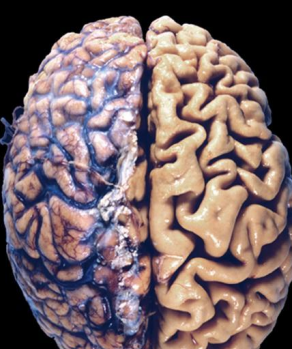

Hipertrofia patológica cardiaca